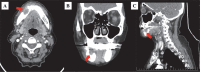

ORNJ의 전형적인 CT 소견에는 뼈 격리, 병리학적 골절, 골용해, 섬유주 구조의 변화, 연조직의 비후, 피질 불연속성 등이 포함됩니다(19, 39)(그림 3). ORNJ의 후기 단계에서 CT 스캔에서 이중피질 침범으로 해면골의 뼈 섬유주가 소실되는 것은 이 질병의 특징적인 특징 중 하나입니다. CT 스캔에서 기포 모양의 병변을 볼 수 있으며, 이는 골수염의 병리학적 감염 과정을 나타낼 수 있습니다(37, 87). 주변 연조직의 비정상적인 성장은 두 번째 원발성 암 또는 종양 재발로 간주하여 둘 중 하나의 가능성을 배제해야 합니다(37). ORNJ는 CT 스캔에서 투과 섬유주 및 골경화증이 보일 때 이러한 상태와 구별될 수 있습니다(88). ORNJ의 진단은 원발성 종양에서 멀리 떨어진 국소 피질 결함에 의해 개선됩니다(89).

컴퓨터 단층 촬영. 우측 하악골 전방의 골방사괴사증은 용해성, 약간 팽창성 및 결함 있는 영역(빨간색 화살표)으로 표시됩니다. A: 축 방향; B: 관상; C: 궁수.

턱의 협측, 설측 또는 양쪽에는 ORNJ와 관련된 피질 불연속성이 있을 수 있습니다. 설측 피질과 해당 협측 피질 모두에서 불연속성의 존재는 턱 골절의 징후로 널리 인식되고 있습니다(85). CT는 2D가 아닌 3D이기 때문에 전후 방향의 뼈 변화와 협측 또는 설측 피질의 침범이 더 잘 보입니다. 또한 OPT는 설측골과 협측골 변성을 구별할 수 없어 CT에서 쉽게 볼 수 있습니다(89, 90). 병리학적 골절이 없는 경우 병리학은 뼈에 국한되지만, 근처에 방추형 부종이 있으면 연조직이 두꺼워지고 병리학적 골절 주위가 침범됨을 나타냅니다(85). 연조직 침범이 없는 경우 하악골 악화는 ORNJ 진단에 도움이 됩니다(91). 진행성 ORNJ와 종양 재발을 구별하는 것은 연조직 부종이 자주 공존하기 때문에 어려울 수 있습니다. 진단을 돕기 위해 악성 편평 세포 암종은 종종 폐포 돌기 또는 설측 피질에 손상을 초래한다는 것을 인식하는 것이 도움이 될 수 있습니다(85). 또한, ORNJ는 RT 또는 CCRT 후 ORNJ 발달 간격의 중앙값이 약 3년인 반면, 종양 재발은 치료 첫 2년 동안 발생하는 경우가 많다는 점에서 종양 재발과 다릅니다(92).